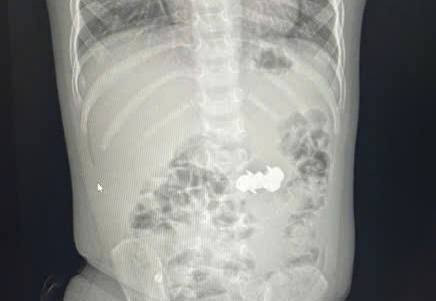

4 đinh nhọn có gắn nam châm được lấy thành công ra khỏi bụng cháu P.

Tiến hành chụp X-quang, các bác sĩ phát hiện trong cháu bé có 4 dị vật kim loại nhỏ hình tròn, có đầu nhọn, nghi là đinh nam châm. Các viên nam châm này đã hút dính nhau trong đường tiêu hoá, tiềm ẩn nhiều nguy hiểm.

Sau hơn một giờ đồng hồ nội soi, toàn bộ bốn viên đinh nam châm đã các y, bác sĩ lấy ra ngoài an toàn. Sau thủ thuật, sức khoẻ của bệnh nhi ổn định, tỉnh táo, ăn uống được và xuất viện về nhà.